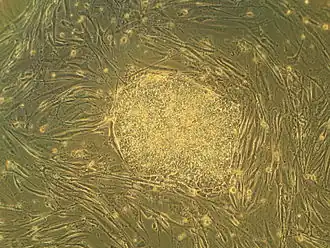

Embryonale stamcellen zijn pluripotente stamcellen die uit een menselijk embryo van slechts enkele dagen oud (4-5 dagen) worden betrokken, voor stamcelonderzoek. Deze stamcellen worden ook wel hESC genoemd, de afkorting van het Engelse human Embryonic Stem cells.

Embryonale stamcellen (ESC's), afkomstig uit het blastocyststadium van vroege zoogdierembryo's, onderscheiden zich door hun vermogen om te differentiëren tot elk embryonaal celtype en door hun vermogen om zichzelf te vernieuwen. Het zijn deze eigenschappen die ze waardevol maken op wetenschappelijk en medisch gebied. ESC's hebben een normaal karyotype, behouden een hoge telomerase-activiteit en vertonen een opmerkelijk proliferatief potentieel op de lange termijn.[3]